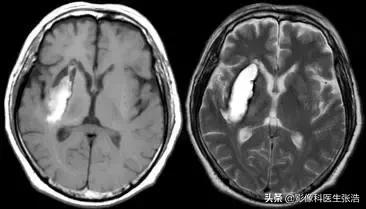

(3)亚急性期:4天至2周内,出血后3-7天为亚急性早期,7-14天为亚急性晚期。

在亚急性早期,去氧血红蛋白被氧化成正铁血红蛋白,它具有5个不成对电子,有很强的顺磁性。脑血肿内正铁血红蛋白首先出现在血肿的周围,并逐渐向血肿内发展。

脑出血亚急性早期

亚急性早期由于正铁血红蛋白形成,T1加权像呈高信号,T2加权像因顺磁性物质的磁敏感效应而呈低信号。

脑出血亚急性晚期

亚急性晚期红细胞开始溶解,在T1或T2加权像上均呈高信号。

红细胞溶解使红细胞对正铁血红蛋白的分隔作用消失,水含量增加是T2加权像信号增高的主要原因。